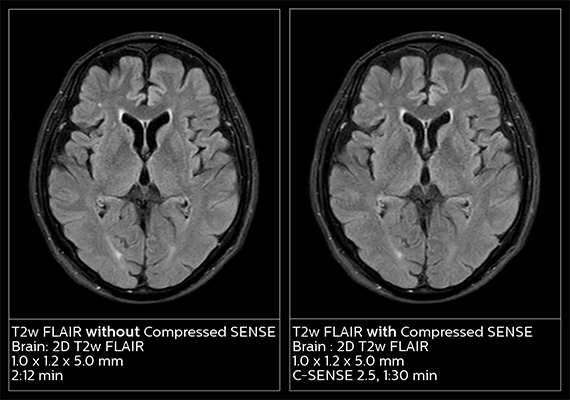

Shortening MR exams without compromising image quality is a pressing challenge in radiology today. Whether in acute care or non-urgent diagnostic circumstances – and for reasons ranging from patient stress to operational costs and throughput – shorter is better. How do you reduce exam time without compromising image quality?

With our innovative MR solution Compressed SENSE, radiology departments can acquire all 2D and 3D scans faster without compromising imaging quality. Philips Compressed SENSE is a breakthrough acceleration technique that speeds up not only sequences, but also the entire exam.